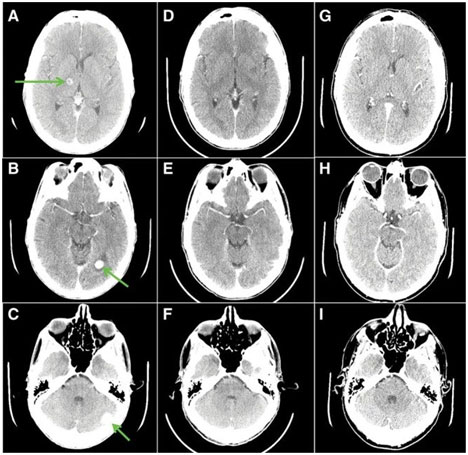

三周后,疼痛癥狀消失,告別吸氧、可以暢快呼吸,并且,全身腫瘤縮少46%,胸壁病灶不見,腦轉(zhuǎn)移瘤大部分消退;5個月后,癥狀不斷改善,全身腫瘤縮小77%,腦轉(zhuǎn)移灶完全消失!

◆用藥前箭頭指的都是腫瘤,用藥26天(D,F)大部分消失, 155 天(G,I)腫瘤完全消失!